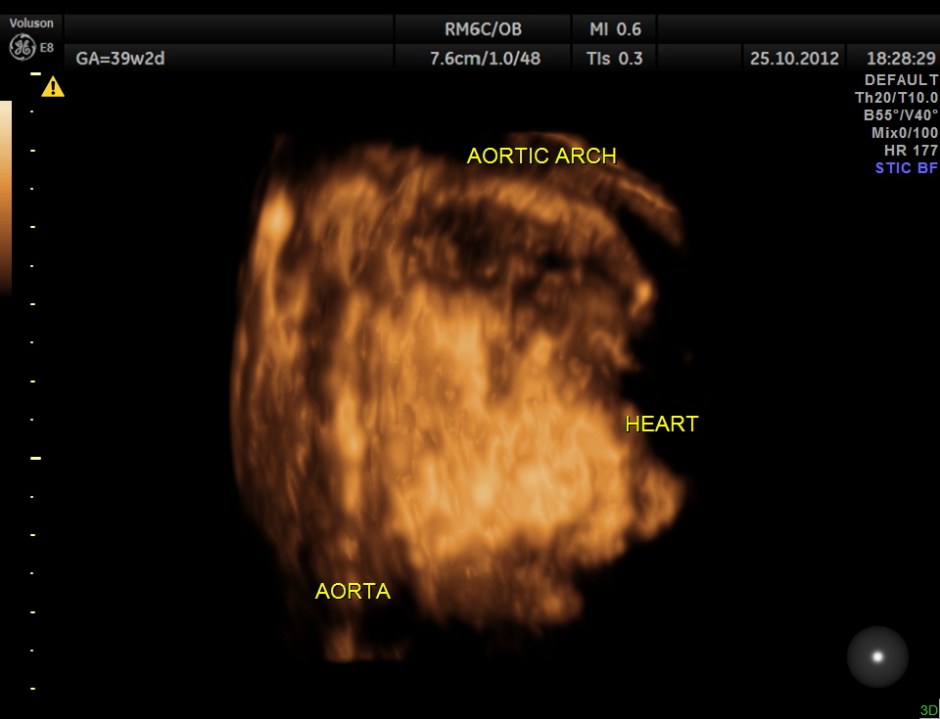

THIS FETUS HAD SEVERE FETAL ANEMIA WITH CARDIAC FAILURE LEADING TO CARDIOMEGALY WITH MITRAL, TRICUSPID AND PULMONARY REGURGITATION .NO OTHER OBVIOUS CARDIAC ANOMALY WAS MADE OUT . THE VENO ATRIAL , ATRIO VENTRICULAR AND VENTRICULO ARTERIAL CONCORDANCE APPEARED TO BE NORMAL; NO SEPTAL DEFECT WAS MADE OUT.